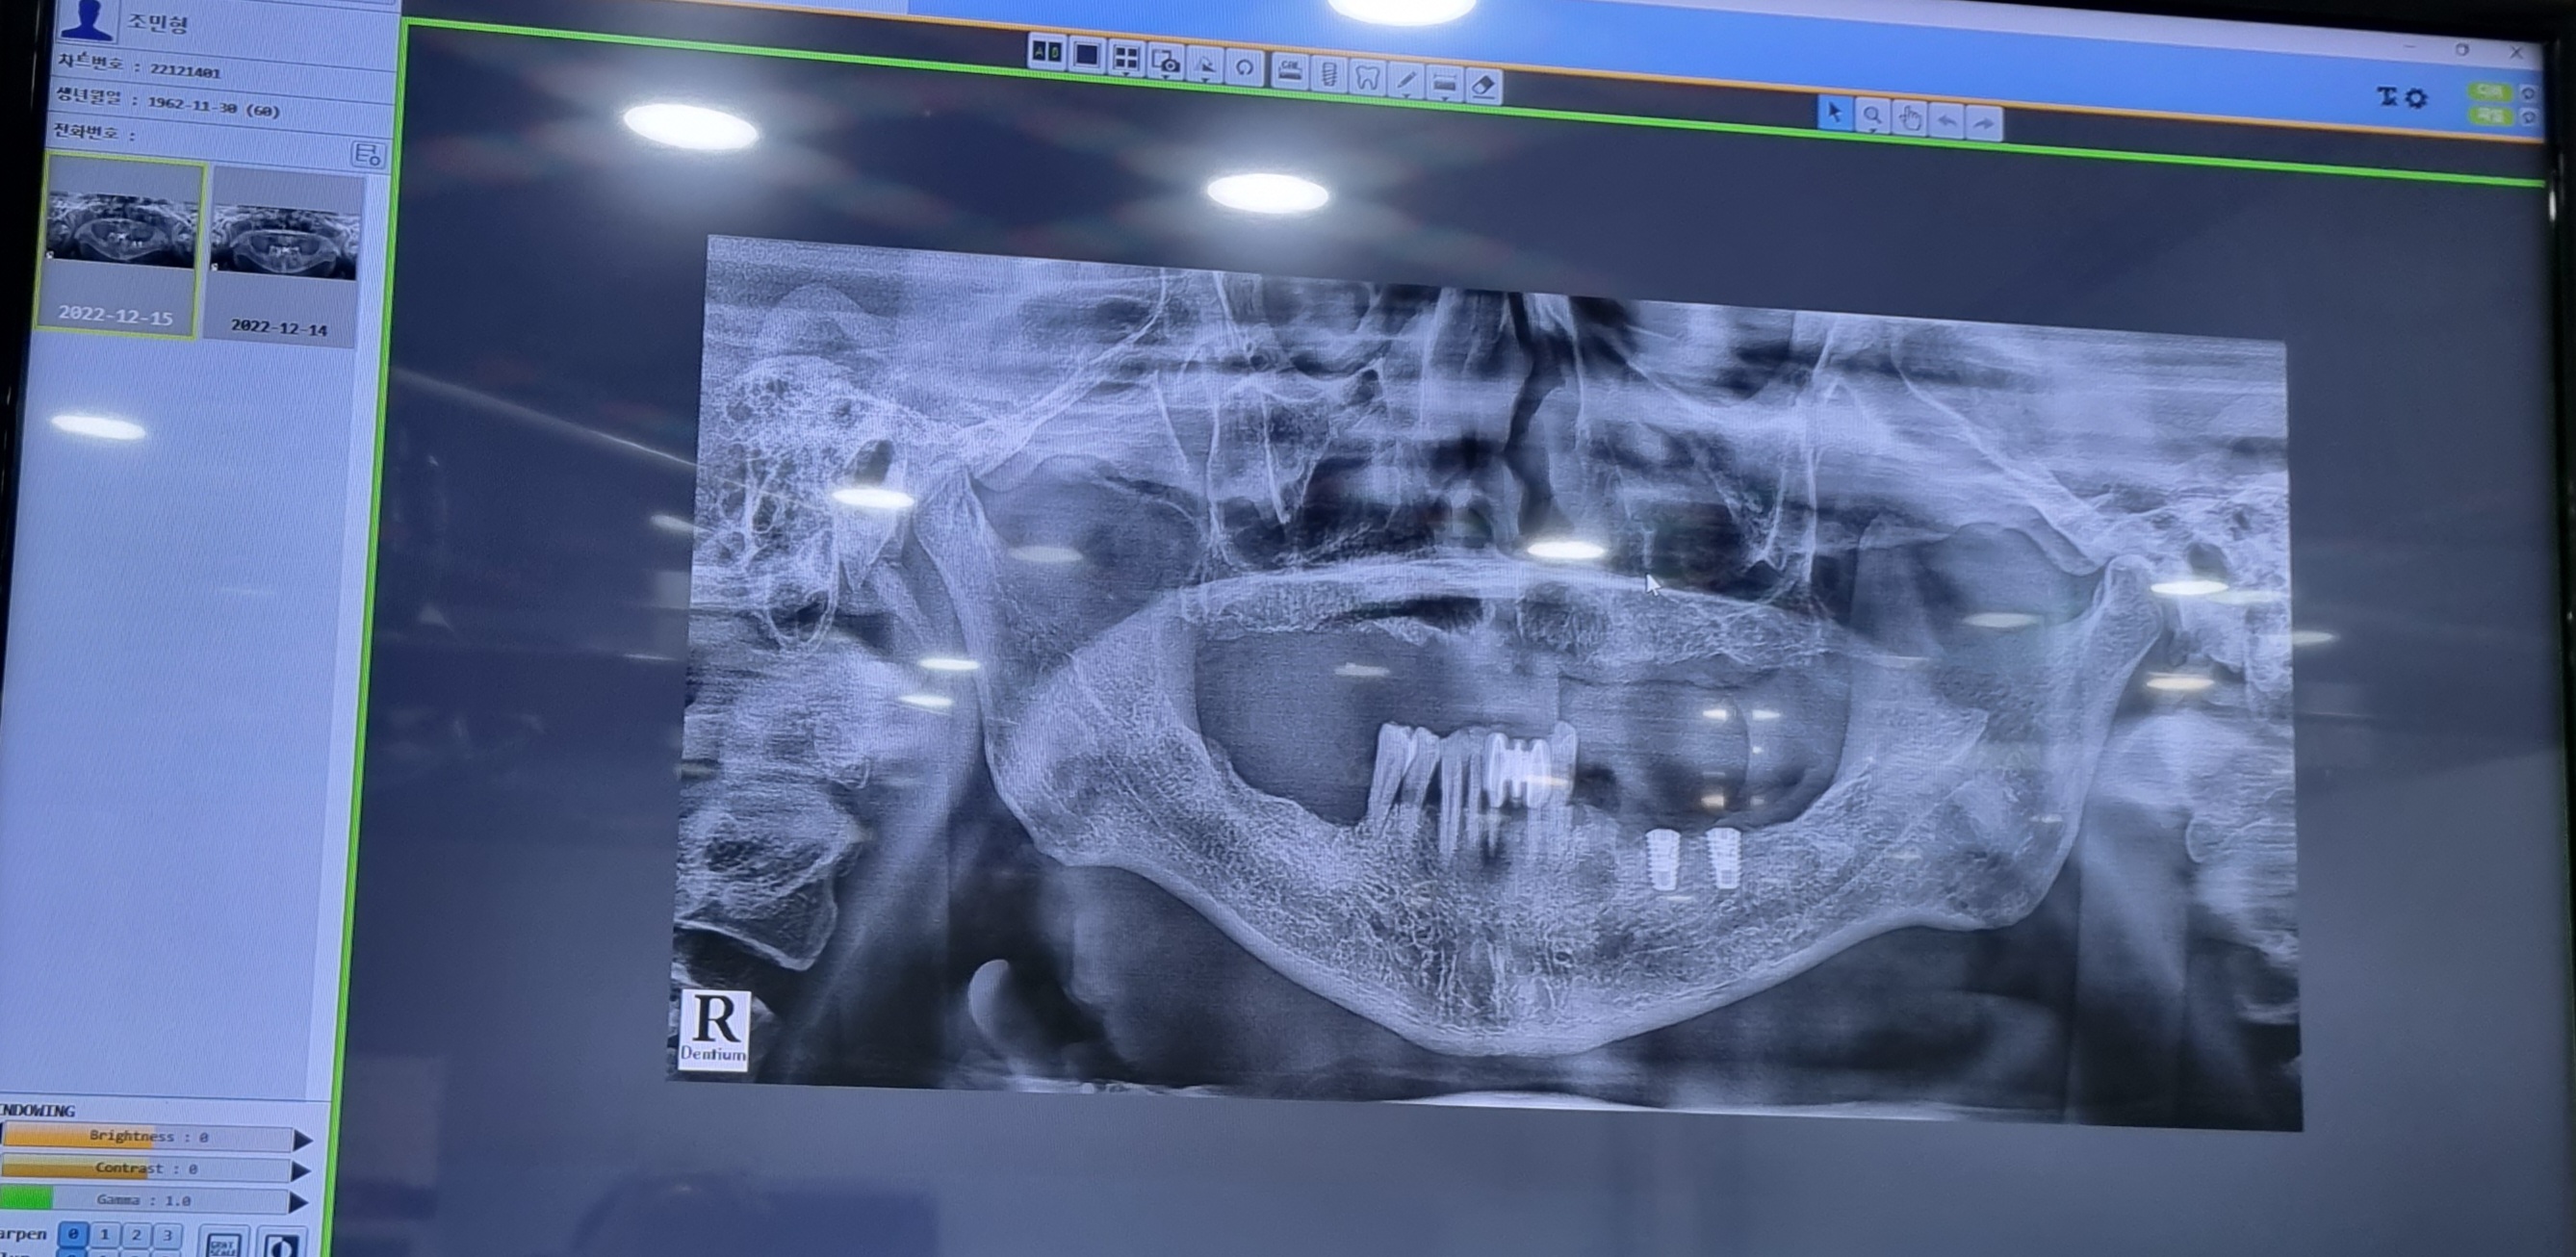

2022 1215 1

아랫니 하악下顎  2개를  발치拔齒후  36. 37 치조골이식술을  뼈속에  심는  과정으로  뼈이식과

임플란트dental implant  수술이  함께  진행하였습니다.